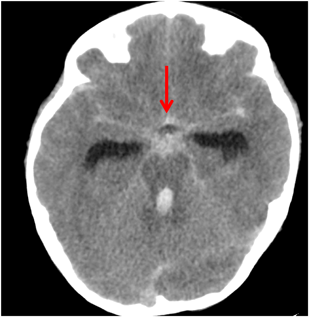

肺動静脈瘻を契機に発見され,脳脊髄動静脈瘻の破裂により死亡した遺伝性出血性末梢血管拡張症の小児2例Hereditary Hemorrhagic Telangiectasia Patients Detected by Pulmonary Arteriovenous Malformations: Two Pediatric Death Cases from Rupture of Cerebral and Spinal Arteriovenous Malformations